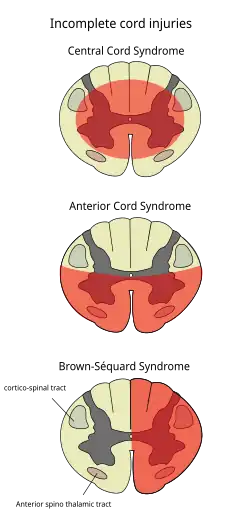

Central cord syndrome

Central cord syndrome, almost always resulting from damage to the cervical spinal cord, is characterized by weakness in the arms with relative sparing of the legs, and spared sensation in regions served by the sacral segments.[25] There is loss of sensation of pain, temperature, light touch, and pressure below the level of injury.[26] The spinal tracts that serve the arms are more affected due to their central location in the spinal cord, while the corticospinal fibers destined for the legs are spared due to their more external location.[26]

The most common of the incomplete SCI syndromes, central cord syndrome usually results from neck hyperextension in older people with spinal stenosis. In younger people, it most commonly results from neck flexion.[27] The most common causes are falls and vehicle accidents; however other possible causes include spinal stenosis and impingement on the spinal cord by a tumor or intervertebral disc.[28]

Anterior spinal artery syndrome

Anterior spinal artery syndrome also known as anterior spinal cord syndrome, due to damage to the front portion of the spinal cord or reduction in the blood supply from the anterior spinal artery, can be caused by fractures or dislocations of vertebrae or herniated disks.[26] Below the level of injury, motor function, pain sensation, and temperature sensation are lost, while sense of touch and proprioception (sense of position in space) remain intact.[29][27] These differences are due to the relative locations of the spinal tracts responsible for each type of function.

Brown-Séquard syndrome

Brown-Séquard syndrome occurs when the spinal cord is injured on one side much more than the other.[30] It is rare for the spinal cord to be truly hemisected (severed on one side), but partial lesions due to penetrating wounds (such as gunshot or knife wounds) or fractured vertebrae or tumors are common.[31] On the ipsilateral side of the injury (same side), the body loses motor function, proprioception, and senses of vibration and touch.[30] On the contralateral (opposite side) of the injury, there is a loss of pain and temperature sensations. If the injury is above pyramidal decussation there is contralateral hemiplegia, at the level of decussation there is completed motor loss on both sides and below pyramidal decussation there is ipsilateral hemiplegia.

[28][30]Spinothalamic tracts are in charge for pain and temperature sensation and because these tracts cross to the opposite side and above the spinal cord there is loss on the contralateral side.[32]

Posterior spinal artery syndrome

Posterior spinal artery syndrome (PSAS), in which just the dorsal columns of the spinal cord are affected, is usually seen in cases of chronic myelopathy but can also occur with infarction of the posterior spinal artery.[33] This rare syndrome causes the loss of proprioception and sense of vibration below the level of injury[27] while motor function and sensation of pain, temperature, and touch remain intact.[34] Usually posterior cord injuries result from insults like disease or vitamin deficiency rather than trauma.[35] Tabes dorsalis, due to injury to the posterior part of the spinal cord caused by syphilis, results in loss of touch and proprioceptive sensation.[36]